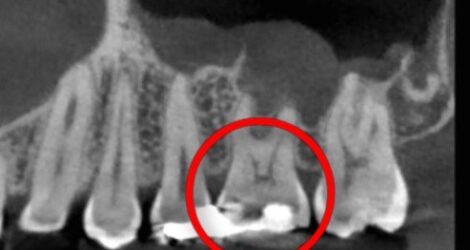

40代男性 上顎第二小臼歯が2次カリエス

口腔内/レントゲン画像

下の部分的なレントゲンになります。

青い部分が虫歯になり、赤色の歯の神経との距離がかなり近くもしくは虫歯で感染が起きている場合があります。痛みなどの症状がなかったため、MTAセメントを使用し神経保護を行なっていきます。